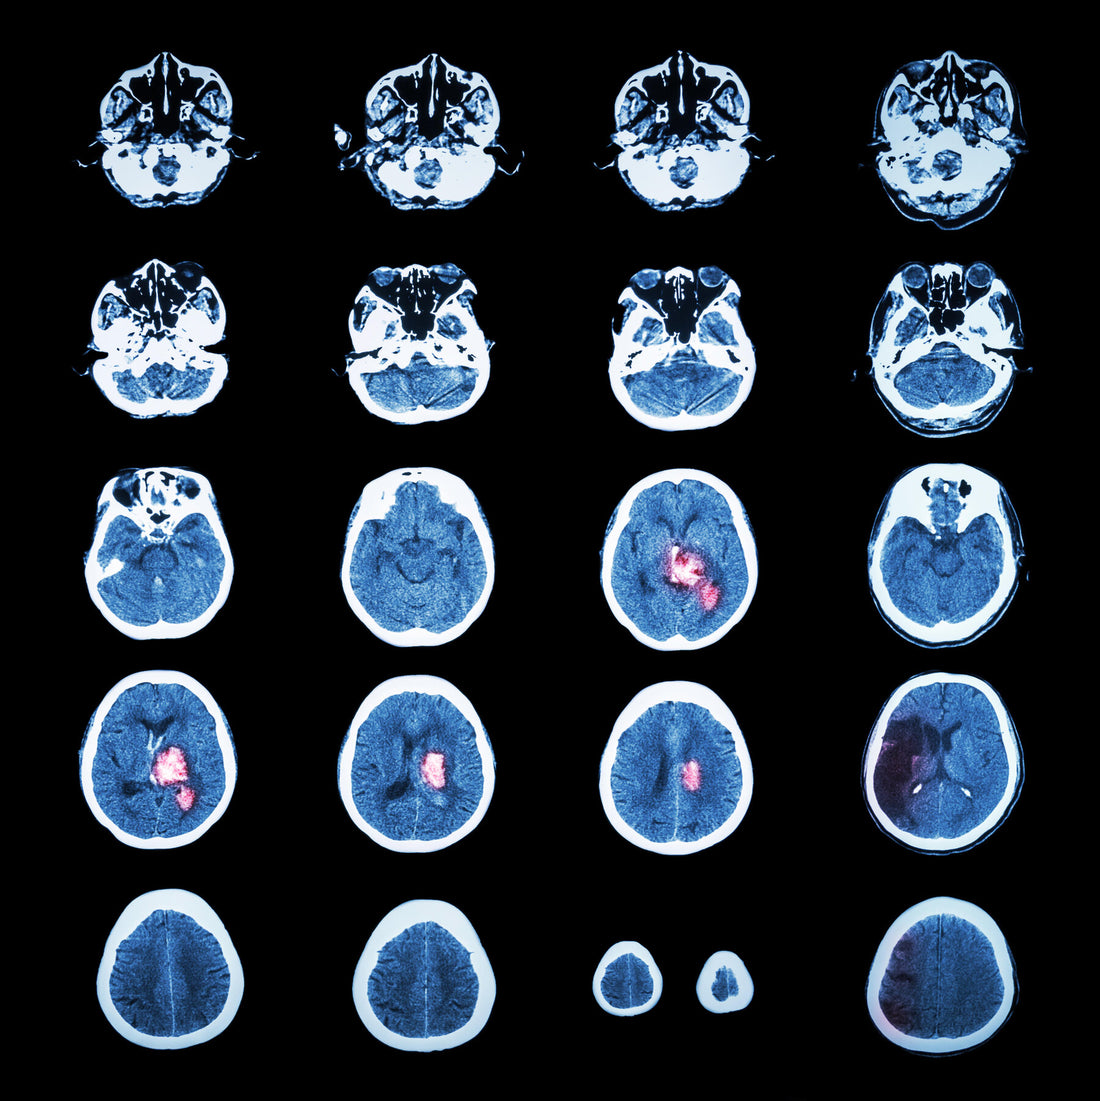

They work for depression and P.T.S.D. Could they also help the brain repair itself after a neurologic catastrophe?